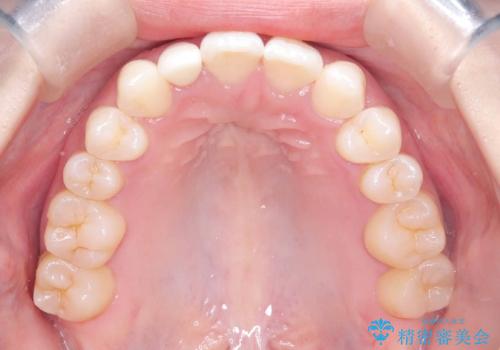

- 歯のデコボコと右上2番の歯の形が気になることを主訴に来院された患者様です。

軽度の叢生(凸凹)であったため、インビザラインのライトパッケージを用いて歯並びを改善しました。その後、右上2番はオールセラミッククラウンにより形態を回復し、審美性を向上させました。

歯並びと見た目がきれいになり、治療も短期間で終わったことから、患者様にも大変ご満足いただきました。